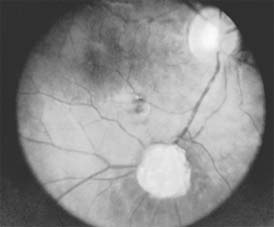

Retinal hemangiomas occur as isolated tumors or associated with cerebellar hemangioblastomas, pancreatic cysts and carcinomas, renal cysts and carcinomas, and pheochromocytomas in von Hippel-Lindau syndrome (Figure 10-30). The retinal tumors are pink or red, endophytic, and usually supplied by a large feeder vessel. Juxtapapillary tumors are usually exophytic. Vision is affected by bleeding or exudation from the tumor vessels. Photocoagulation, diathermy, and cryotherapy are used to treat the retinal lesions.

Figure 10-30

Figure 10-30: Angiomatosis retinae of Von Hippel-Lindau disease (drawing). (Courtesy of F Cordes.)